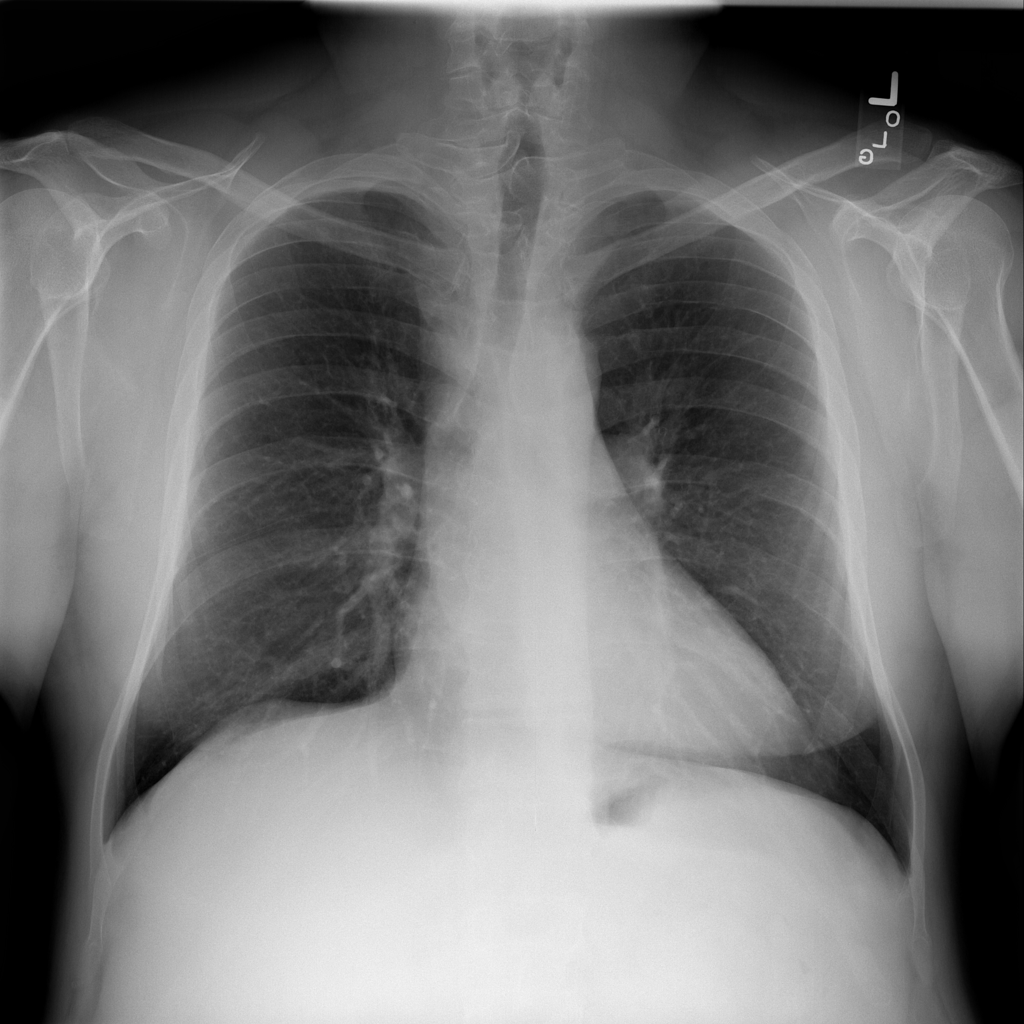

Mass

A mass is a larger focal opacity or lesion seen on the image. It is a descriptive finding that can have several causes and usually needs more imaging or clinical context to characterize.

PAT-50E5 · IMG-008Mass

PAT-50E5 · IMG-008

PA